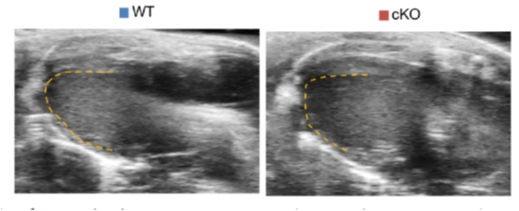

新生小鼠Agrin敲除的效用:心肌纤维化、心功能下降